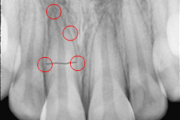

Krooni murd